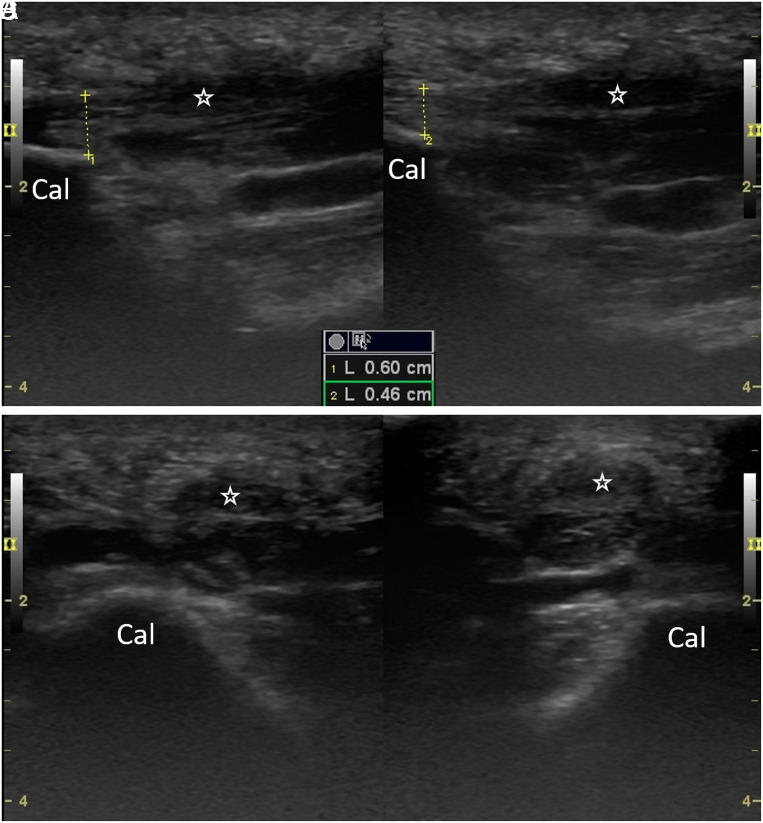

Plantar Fibromatosis/Fascitis in Ankylosing Spondylitis: Why/Where to Inject?